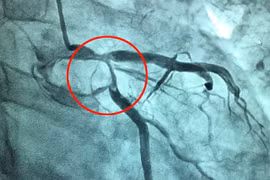

Nhiều bệnh nhân bị liệt, hoại tử ngón chân hoặc phải cắt bỏ cả chi mới biết mình bị bệnh tắc động mạch chi chứ không phải đau xương khớp. Mùa đông lạnh, ẩm gây co thắt mạch máu khiến bệnh tắc động mạch chi gia tăng từ 10 – 15%.

Nhiễm trùng từ vết chó cắn khiến cụ chân cụ ông 95 tuổi bị hẹp mạch máu gây tắc mạch hoại tử chi. Dù được nong mạch nhưng tiên lượng dè dặt nguy cơ phải cắt cụt.

Cụ bà 72 tuổi (Hà Nội) mới khỏi Covid-19 được 1 tháng, đột ngột bị đau nhức chân phải, toàn bộ đùi và cẳng chân phải lạnh ngắt và tím tái, cử động rất hạn chế...